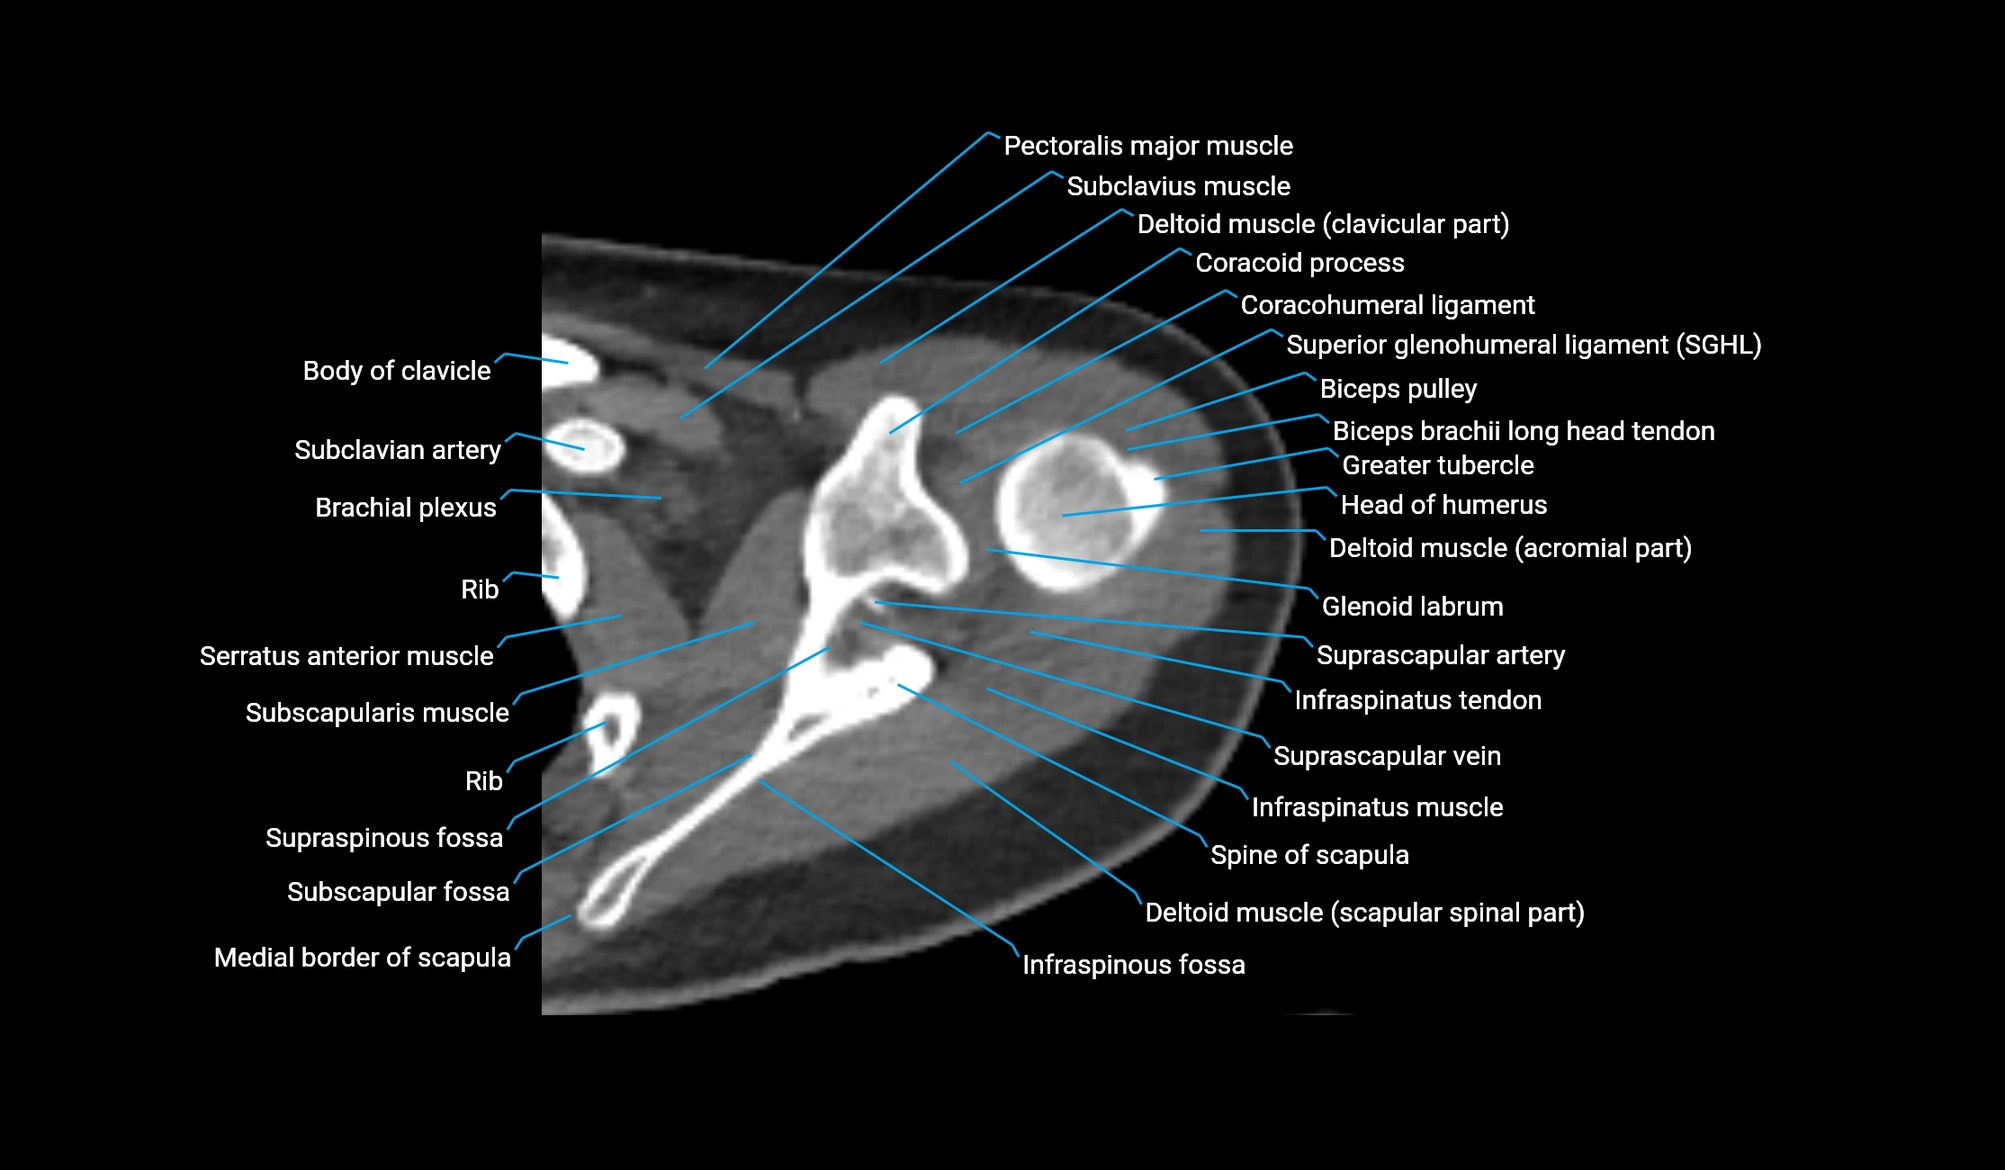

CT image